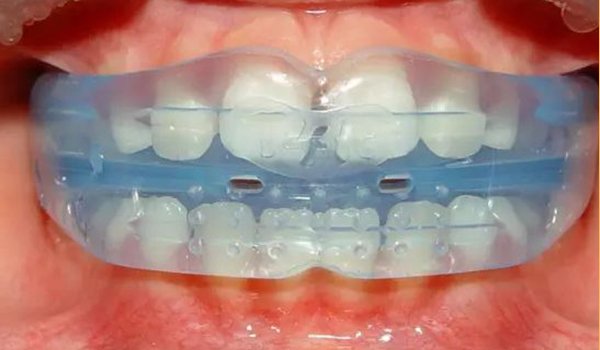

3D数码隐形正牙

美观时尚 · 外观透明隐形

效果预知 · 可见正牙效果

方便省时 · 可自行摘戴